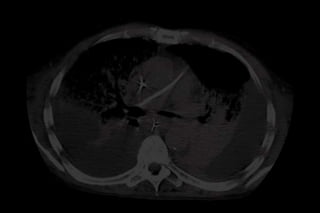

CLASSIFICAÇÃO SEGUNDO

A MORFOLOGIA PULMONAR

Grupo HL

(Hiperdensidades Localizadas):

Hiperdensidades      radiológicas

delimitadas     por        estrutura

anatômica,    como     a    grande

cissura;

Gusman P.B., 2000

Grupo HD

(Hiperdensidades Difusas):

Hiperdensidades   difusas     e

não delimitadas por estrutura

anatômica;